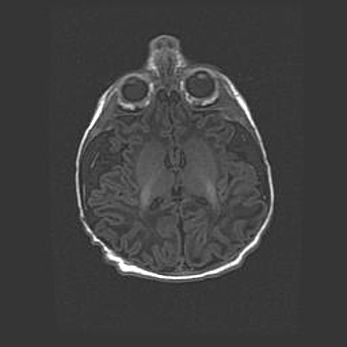

Лейкомаляция с кистозно-глиозной дегенерацией головного мозга.

Возраст: 2 месяца 25 дней

Вес: 6400 г

Окружность головы: 40 см

Срок гестации: 41 неделя

Лейкомаляцию относят к ишемически-гипоксическим повреждениям головного мозга, диагностируемым у новорожденных. При лейкомаляции в головном мозге обнаруживают очаги некроза, возникшие после тяжелой гипоксии и нарушения кровотока. В процессе морфогенеза очаги проходят три стадии: 1) развития некроза, 2) резорбции и 3) формирования глиозного рубца или кисты. Перивентрикулярная лейкомаляция (ПЛ) встречается примерно в 12% случаев среди новорожденных, обычно – у недоношенных детей, причем, частота ее зависит от массы, с которой младенец появился на свет. Наибольшее число малышей страдает лейкомаляцией, если масса при рождении 1500-2500 г.